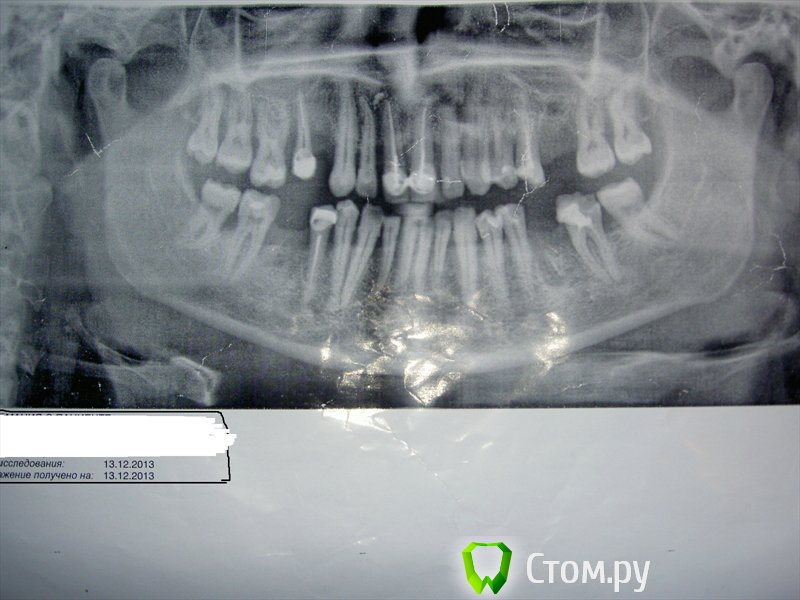

IvanK Опубликовано 23 января, 2014 Поделиться Опубликовано 23 января, 2014 Вылечены замечательно. По моему мнению, пациент не может оценить Врача... Можно было бы попробовать его депульпировать, но, может и не получиться пройти каналы, тогда на удаление тактика не правильная Выложите панорамный снимок Ссылка на комментарий

KOV Опубликовано 23 января, 2014 Автор Поделиться Опубликовано 23 января, 2014 Пациенту приходится жить с последствиями лечения Врача. На мой взгляд, более аргументированной оценки трудно придумать.Тактика по 48-му мне,тоже, не понравилась, поэтому, он, пока на месте...Есть панорамный снимок до лечения. Будет в нём смысл? Ссылка на комментарий

IvanK Опубликовано 23 января, 2014 Поделиться Опубликовано 23 января, 2014 Пациенту приходится жить с последствиями лечения Врача. На мой взгляд, более аргументированной оценки трудно придумать. без комментариев Есть панорамный снимок до лечения. Будет в нём смысл? для общей картины - да Ссылка на комментарий

KOV Опубликовано 23 января, 2014 Автор Поделиться Опубликовано 23 января, 2014 Снимок сделан 13 декабря 2013г. До лечения. Ссылка на комментарий